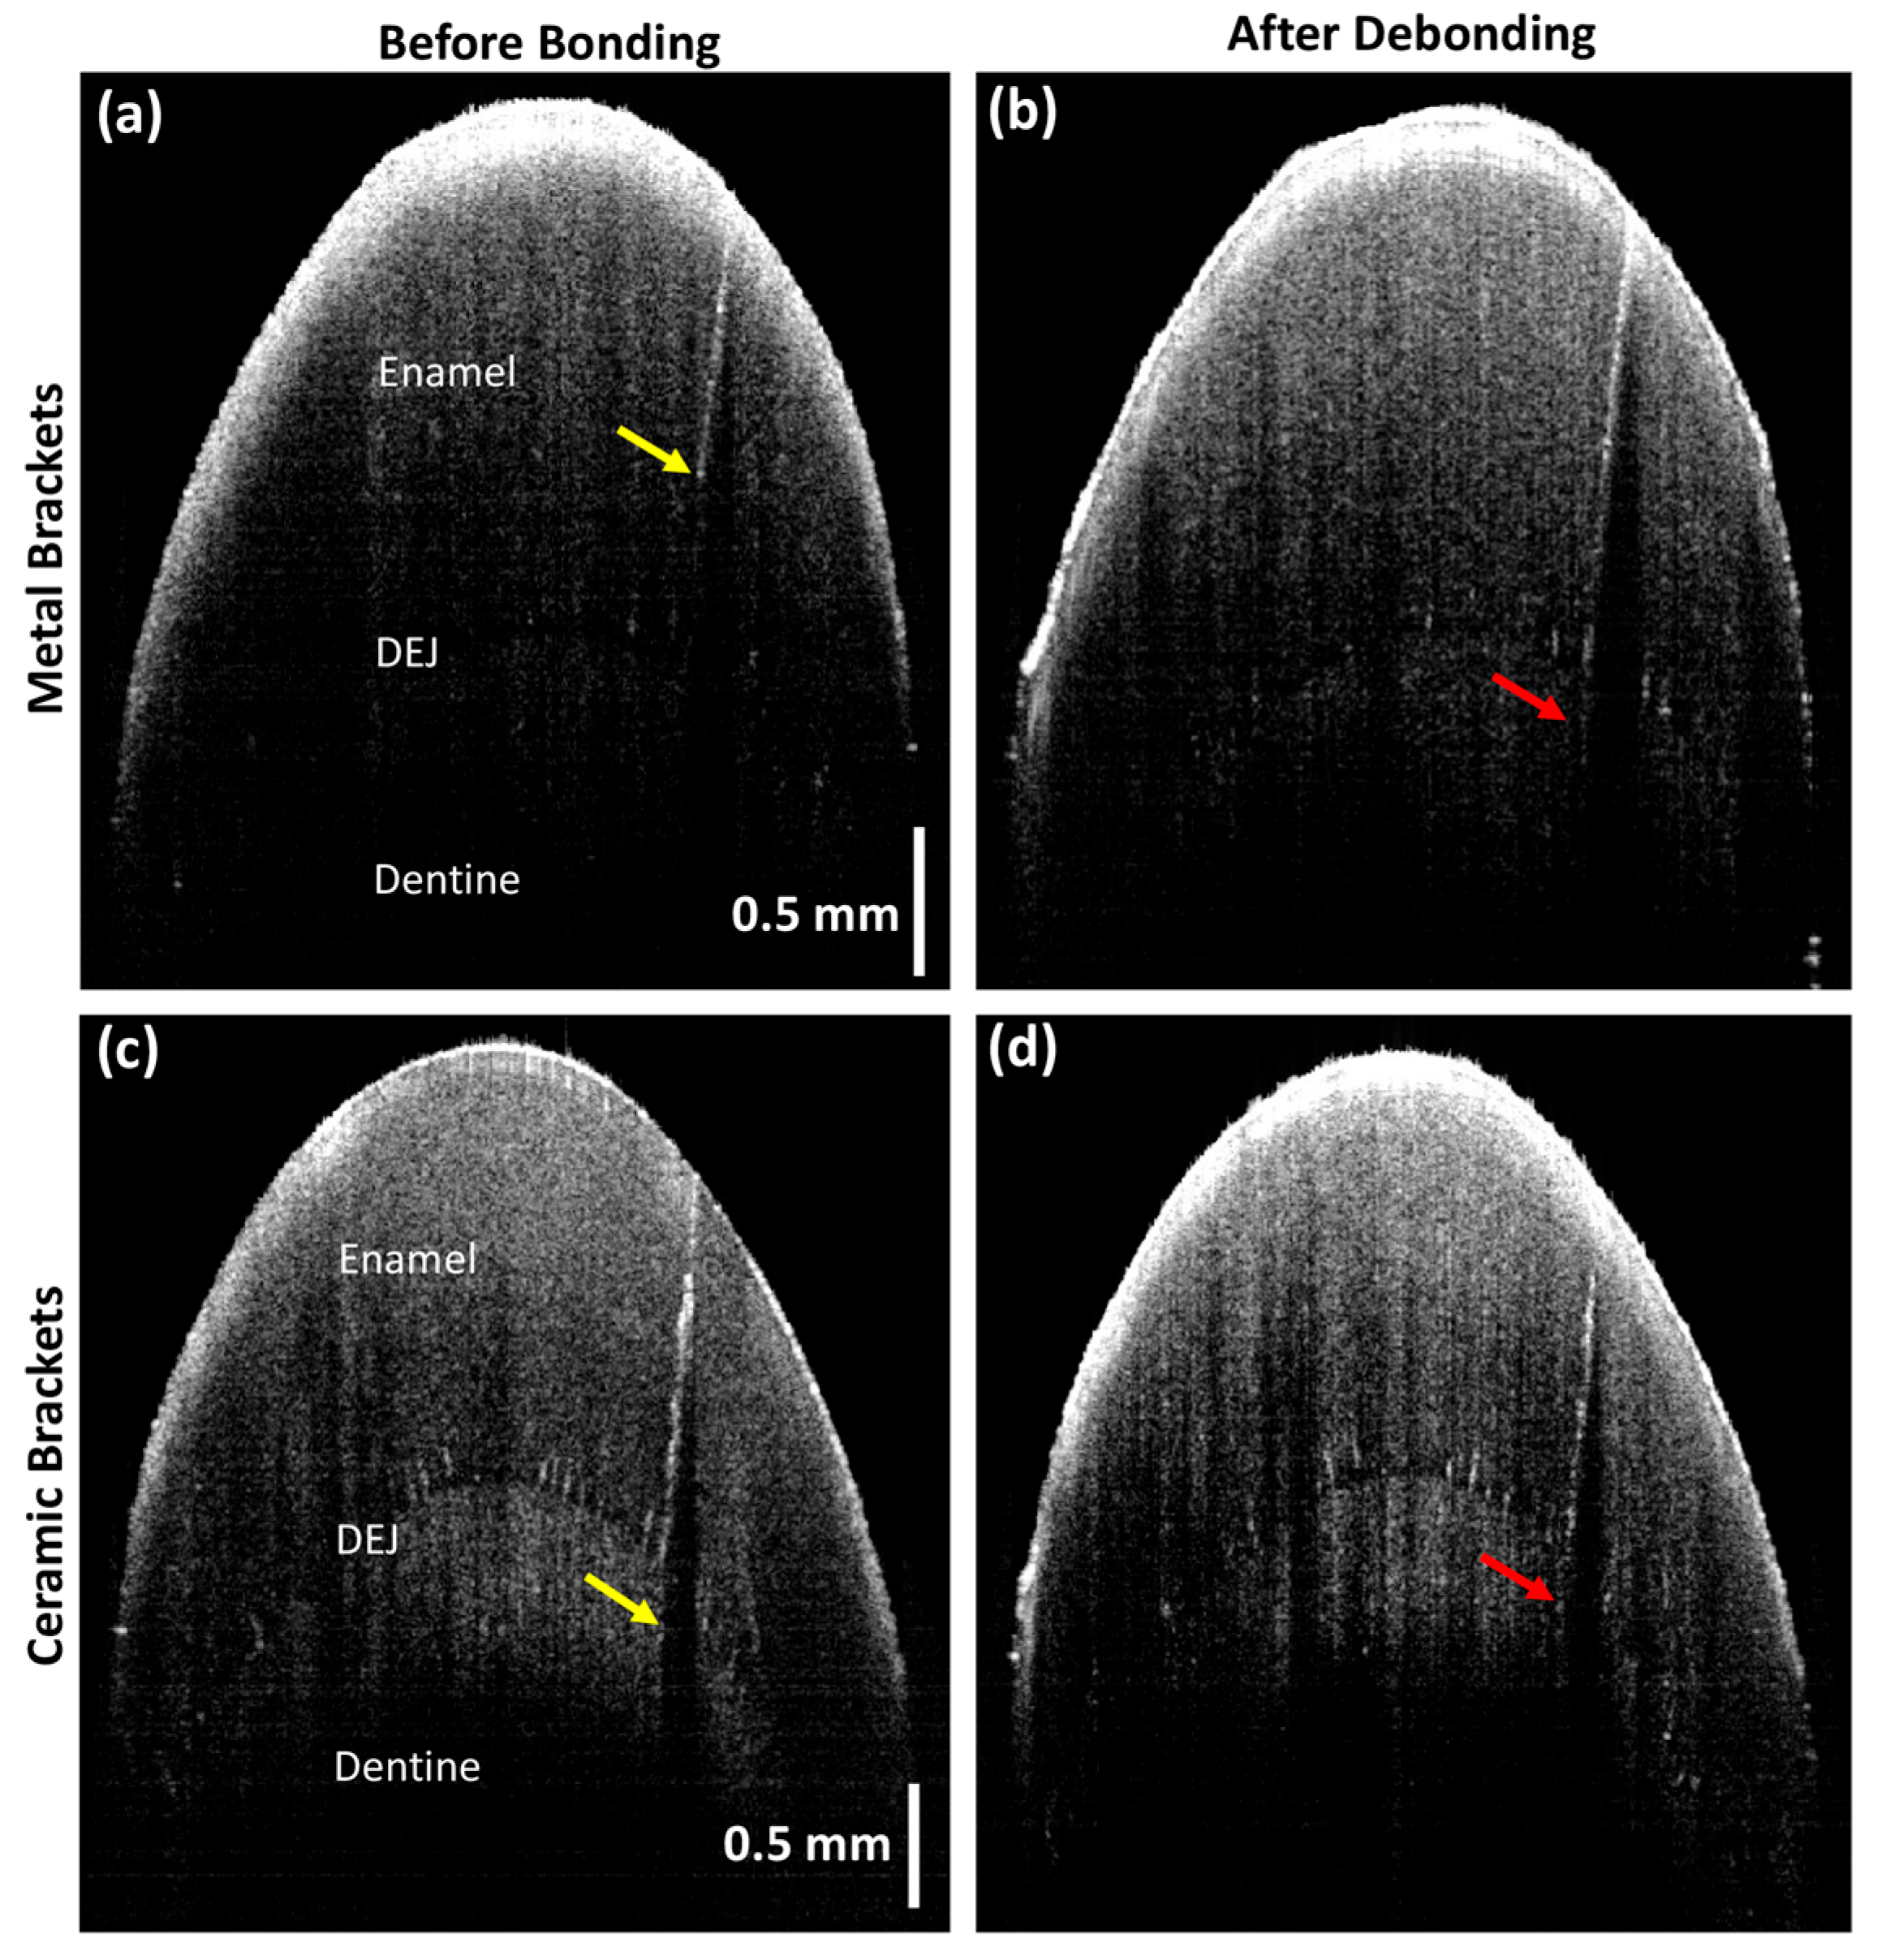

Progression in the depth of the EMCs was observed in three samples with metal brackets and five with ceramic brackets. The differences were statistically significant in the total sample (p-value = 0.009) and the ceramic group (p-value = 0.038) but not in the metal group (Table 1, Figure 5 and Figure 6).

Figure 5.

Three-dimensional cross-sectional images illustrating EMC progression: (a) no cracks visible on the buccal surface before bonding; (b) pre-existing crack with a depth index score of 3 seen on the enamel surface before bonding (red arrow); (c) side view of the dental 3D image; (d) formation of new EMC and (*) vertical and (#) horizontal expansion of pre-existing crack (increase in depth index score from 3 to 5) visible after debonding (red arrows). The red dotted lines in (a) indicate the 3D cross-sectional positions of (b,d).

Figure 6.

Two-dimensional sagittal cross-sectional OCT images indicating EMC progression. The cross-sectional view shows the enamel layer, dentin–enamel junction (DEJ), and dentine layer. (a,c) EMC depth index before bonding (yellow arrows) and (b,d) EMC depth index progression after debonding (red arrows) in the metal and ceramic brackets, respectively.

This study found a significant propagation in EMCs after debonding, with an overall average length increase of approximately 20.6% (metal: 13.21%; ceramic: 26.9%). The EMC width had increased significantly by 105% (metal: 96%; ceramic: 112%). Since EMC depth measurements can be precisely achieved for EMCs extended only within the enamel layer, the EMC depth index scale was implemented in the current study. The depth index showed that 50% of the total sample displayed depth progression (metal: 42.8%; ceramic: 55.5%). In addition, the 2D and 3D OCT images confirmed the formation of new EMCs after debonding (Figure 3 and Figure 5). Approximately 43.8% of the study sample (n = 7/16) exhibited newly formed EMCs (metal: 66.6%; ceramic: 33.3%). However, the progression of EMCs was not coincident with the recent systematic review and meta-analysis study [41], which may be attributed to the advanced imaging with OCT. The wide range in the standard deviation in the current study was related to the variation in the EMC size between the samples but not to the measurements. However, the statistical tool, a paired t-test, allowed the detection of the progression of EMCs. Nevertheless, the current study introduced a novel approach by incorporating OCT enface images and the ImageJ software to measure the EMC length (Figure 3) and the depth-intensity profile algorithms that provided micrometer measurements of the EMC width (Figure 4).